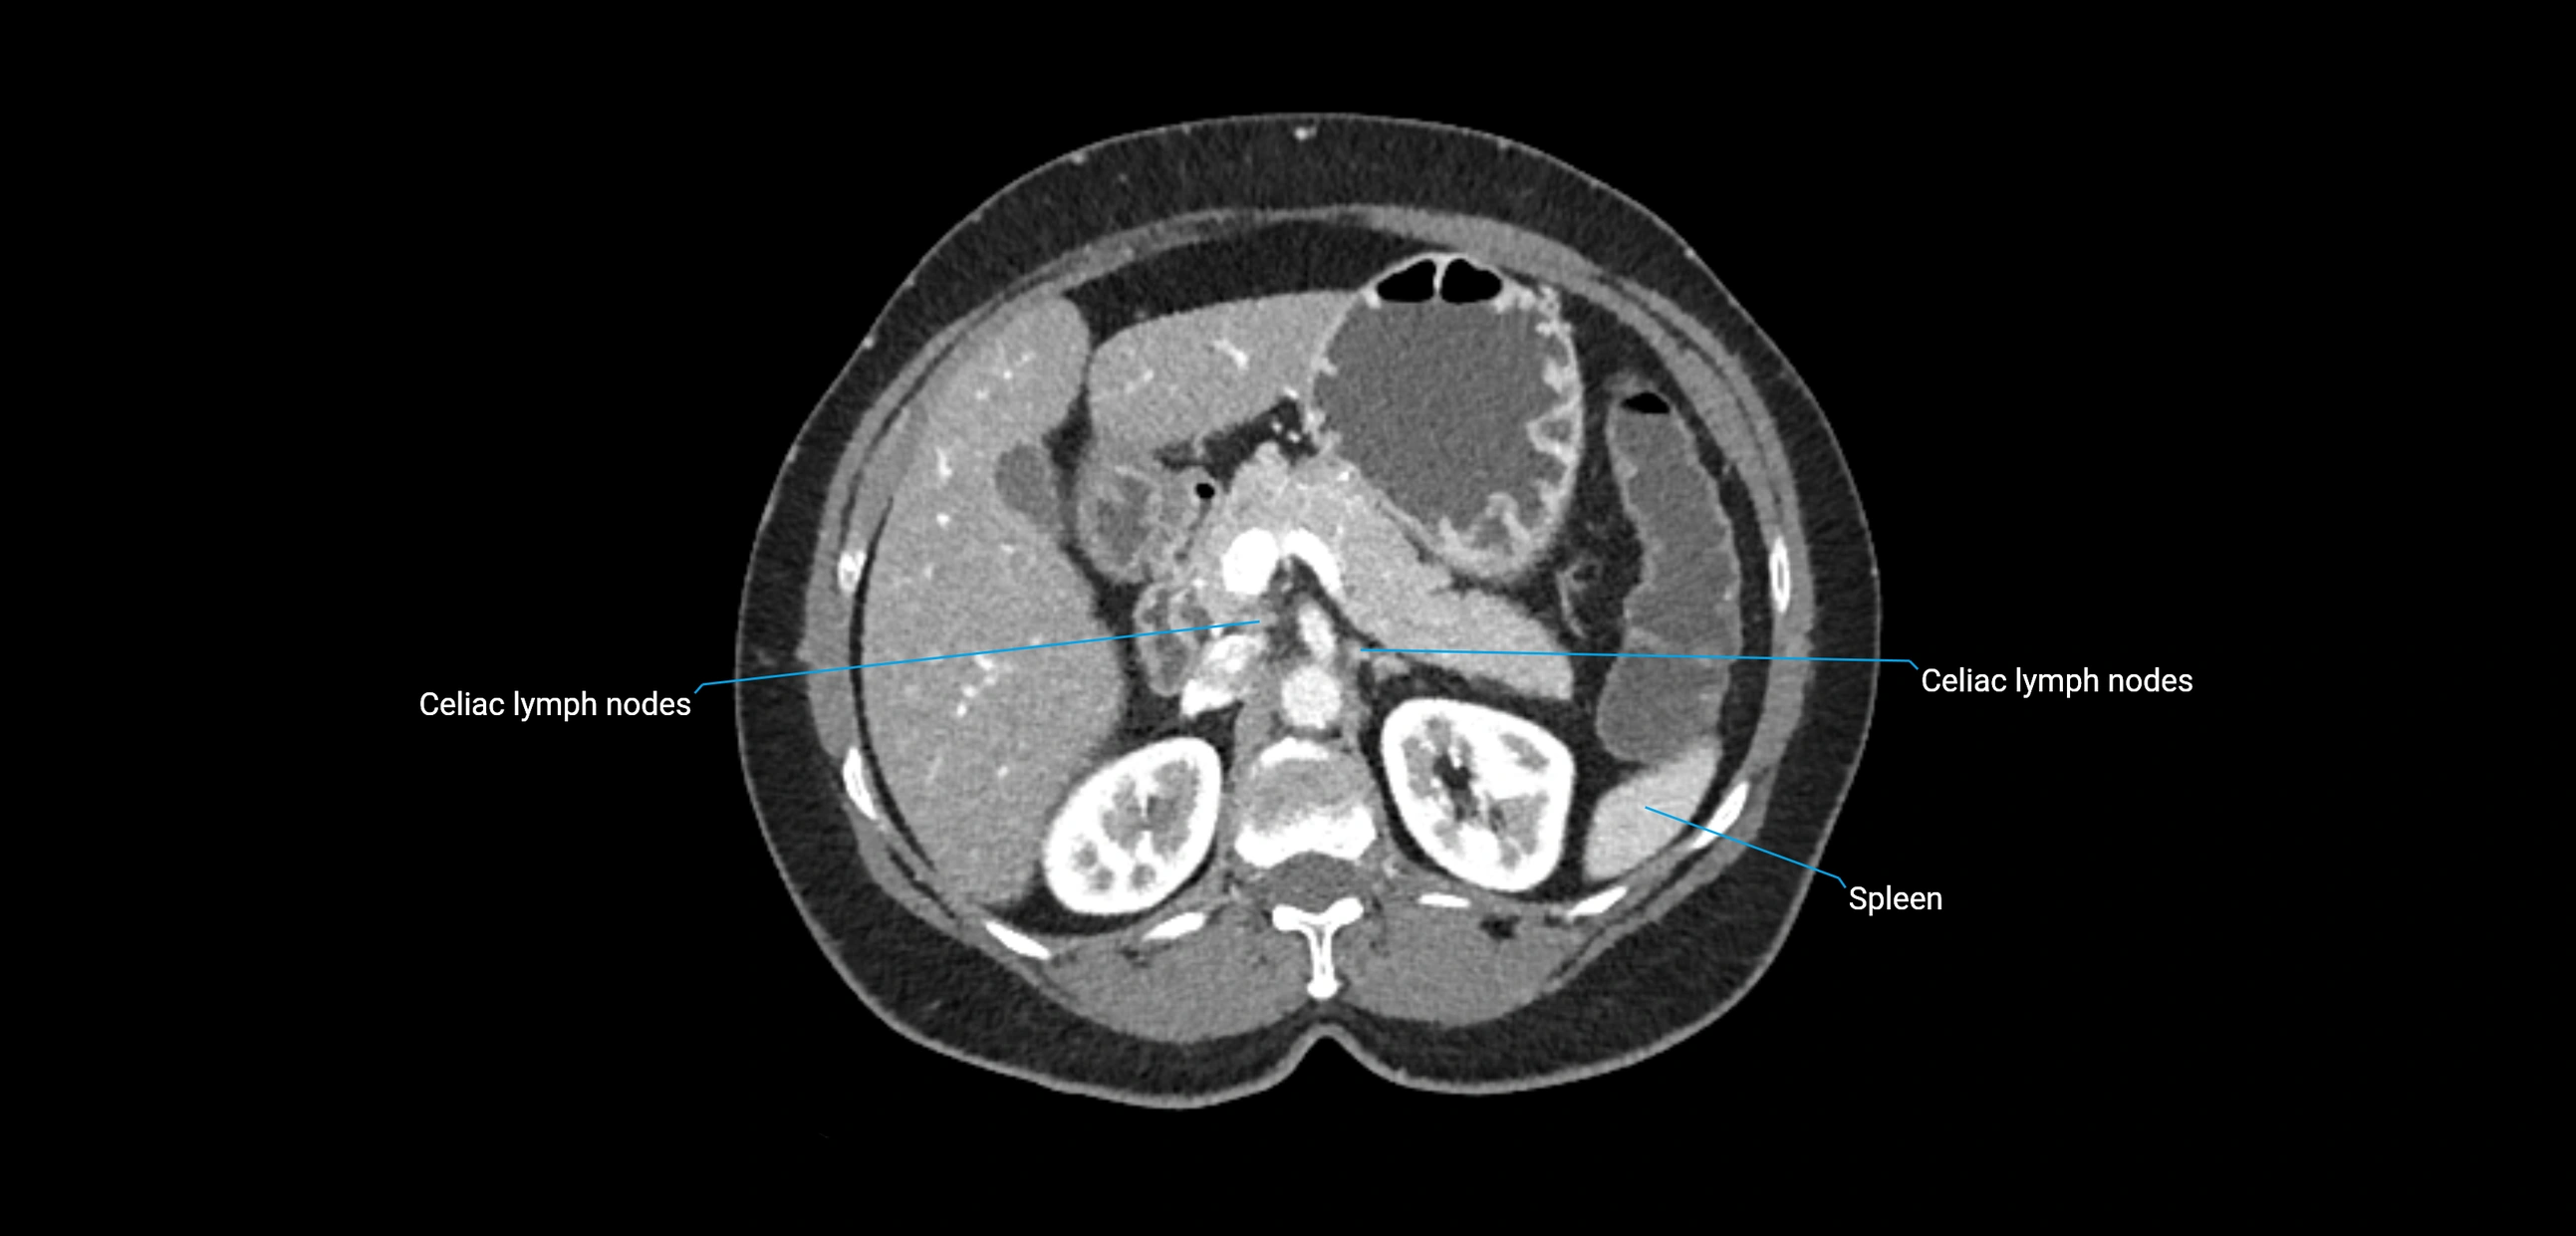

CT Appearance

CT Pre-Contrast:

• Nodes appear as soft-tissue density nodules adjacent to the aorta and IVC

• Calcification may be seen in chronic infections (e.g., tuberculosis)

CT Post-Contrast:

• Normal nodes enhance homogeneously

• Malignant nodes may show heterogeneous enhancement, central necrosis, or conglomerate formation

• Size >1 cm short axis is suspicious, though morphology and distribution are equally important